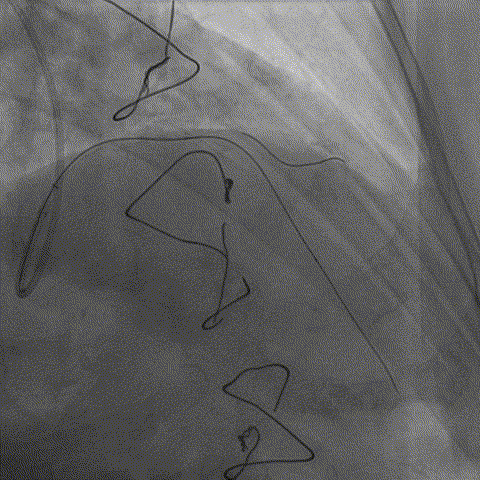

冠脉造影

考虑病人前降支闭塞伴有钙化严重,应用强支撑导管,开通应用导丝feilder XT-R,考虑头臂干血管迂曲,必要时改股动脉,如果指引导管顺利到位,可以选择导引延长导管增加支撑力,辅助送入球囊及支架。

• 之前对手术指引导管估计有误,选择BL3.0支撑力不够,改换EBU3.5,导丝过病变但球囊过不去,手术期间EBU3.5不能下入窦底,用导引延长导管引导进入窦底,开始选用1.0*10到2.5*15升级球囊扩张病变。

• 导引延长导管操作过程中的作用是什么?第一应用其顺利通过迂曲头臂干进入窦底,第二增加支撑力送入球囊,辅助送入支架及后扩球囊。